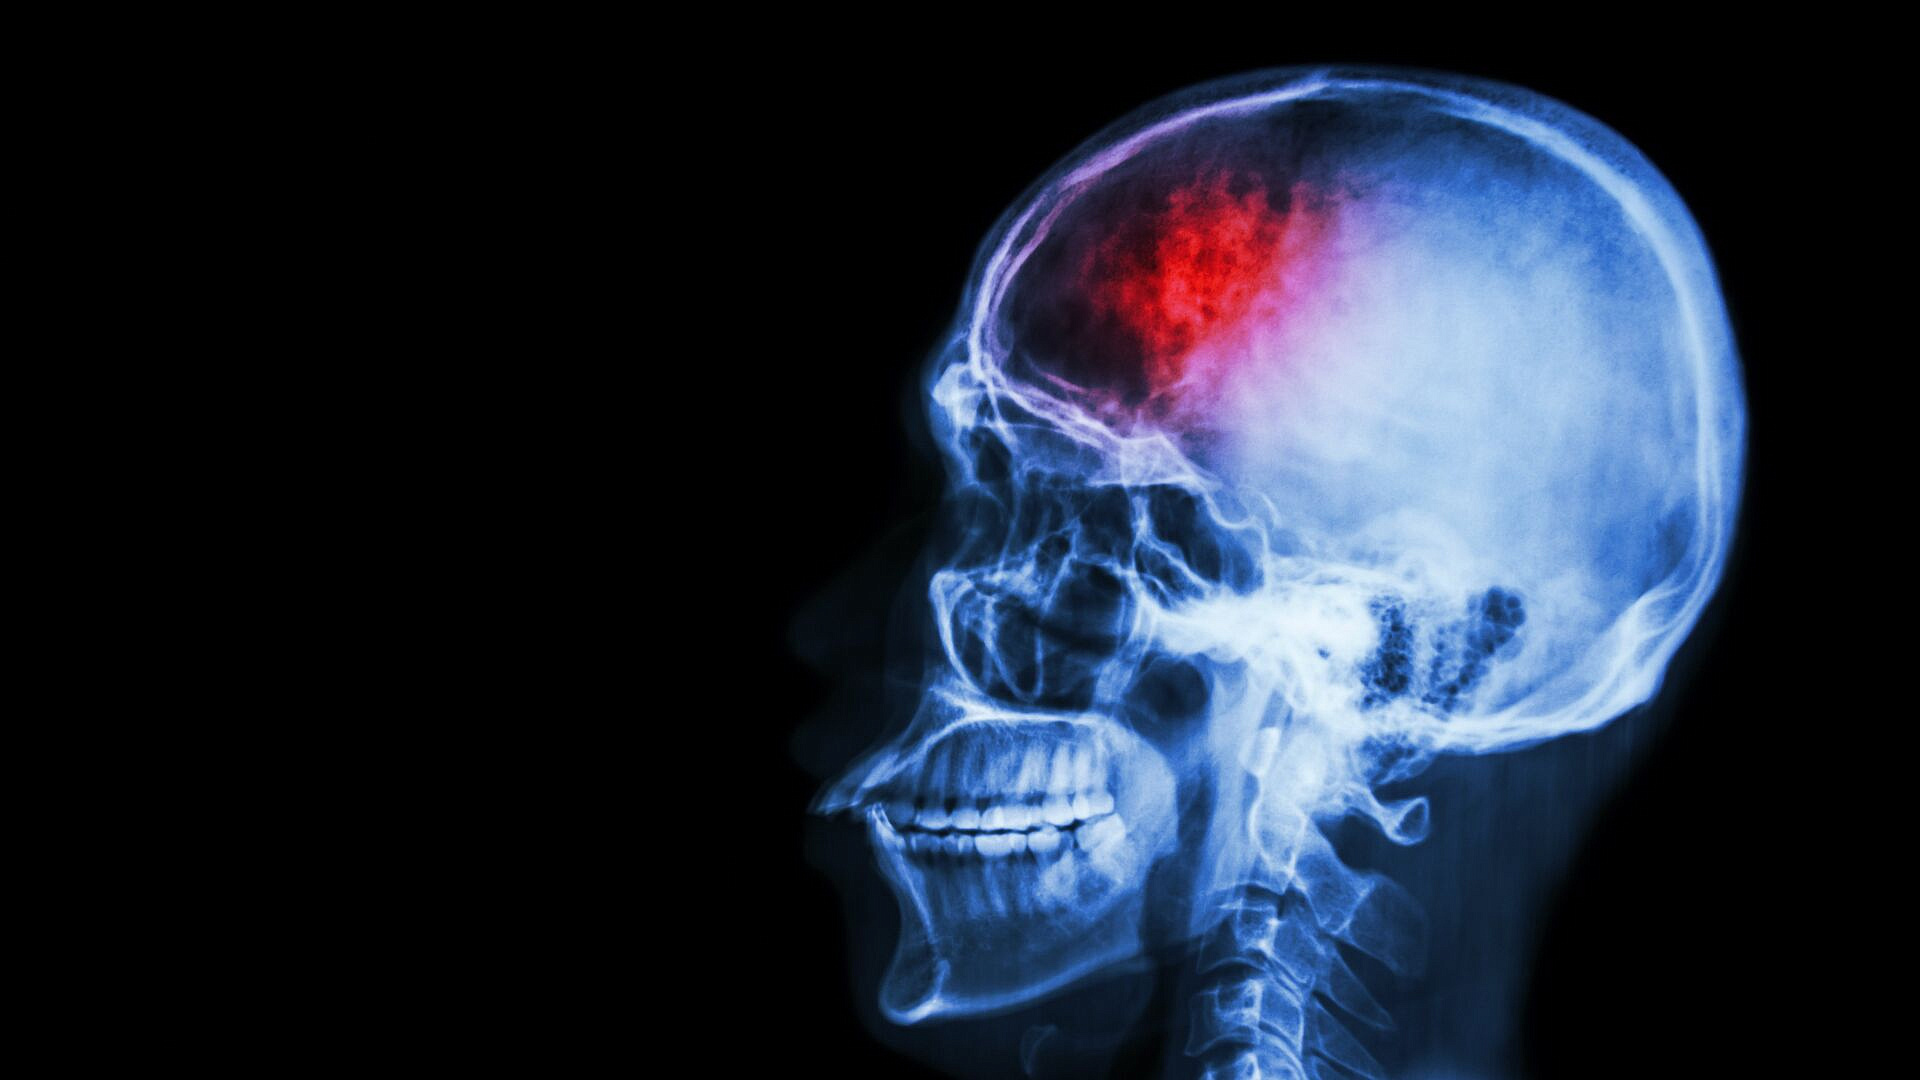

Невролог назвал факторы риска развития инсульта

Люди с повышенным артериальным давлением, избыточным весом, ожирением, высоким уровнем холестерина в крови, неритмичным сердцебиением и диабетом находятся в группе риска для развития инсульта, сообщил врач-невролог Владимир Мартынов.

Для снижения вероятности инсульта рекомендуется проходить ежегодную диспансеризацию для выявления факторов риска, таких как гипертония. Необходимо регулярно контролировать артериальное давление и при необходимости принимать соответствующие препараты. Избыточный вес и ожирение также увеличивают риск инсульта, поэтому важно придерживаться здорового питания и ограничить потребление соли. Атеросклеротические бляшки, обусловленные высоким уровнем холестерина, а также фибрилляция, приводящая к образованию тромбов, могут способствовать развитию инсульта. Регулярное контролирование уровня холестерина и сахара в крови, при необходимости прием статинов, антикоагулянтов или антидиабетических препаратов рекомендуется только по назначению врача.